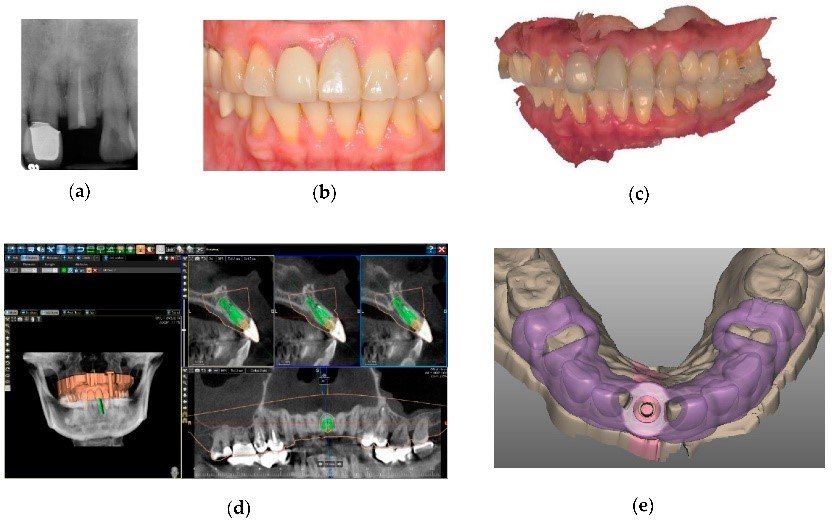

3. Digital Wax-Ups & Prosthetically Driven Planning

In modern implantology, prosthetically driven planning has become a fundamental approach to ensure the long-term success, functionality, and aesthetics of dental implants. Rather than placing implants based solely on bone availability, this method prioritizes the final prosthetic outcome, ensuring implants are positioned to best support the restoration, occlusion, and overall oral function.

A critical component of prosthetically driven implant planning is the use of digital wax-ups—virtual models that allow clinicians to visualize the final restoration before any surgical intervention occurs. These wax-ups, created through computer-aided design (CAD) software, help plan the ideal implant positioning, angulation, and emergence profile, minimizing complications and maximizing patient satisfaction.

Digital wax-ups are three-dimensional virtual models of a patient’s proposed final prosthetic restoration created using digital dentistry software. These models mimic the natural anatomy, occlusion, and esthetic contours of the intended dental work, enabling precise preoperative planning.

- Intraoral scanning captures the patient’s existing dentition, soft tissue, and bite relationship.

- CBCT imaging provides three-dimensional visualization of bone structure and anatomical landmarks.

- The data is imported into CAD software, where the ideal prosthetic design is created digitally.

- The digital model allows for pre-surgical modifications and simulations, ensuring optimal implant positioning and esthetic results.

3. Integration of Digital Wax-Ups with CBCT & Intraoral Scanning

A predictable implant placement requires the seamless integration of CBCT imaging, intraoral scanning, and digital wax-ups.